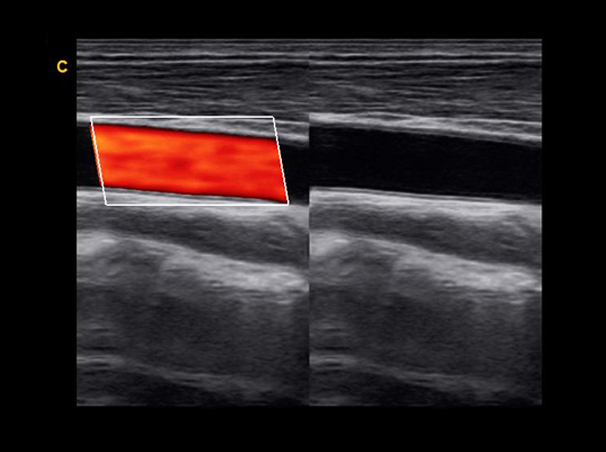

Carotid,BBC Mode